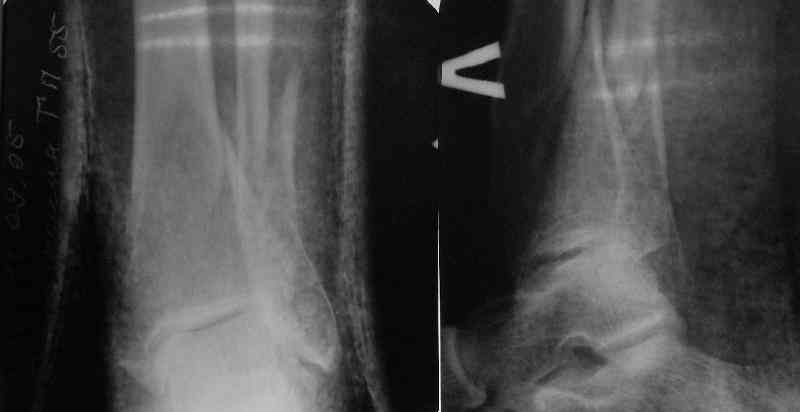

TDVC> Very interesting application, but is the final position in a

TDVC> little distal varus with some fibula distraction?

At least both the ankle mortise and tibial alignment look acceptable, don't they?

TDVC> Would that have been eliminated by fibula plating?

I am just trying to illustrate that prevention of 1)tibial valgus and 2)loss of reduction can be provided without fibular plating. Small changes of conventional nailing techniques allow to maintain reduction of the tibia reliably without adjunctive fibular stabilization.